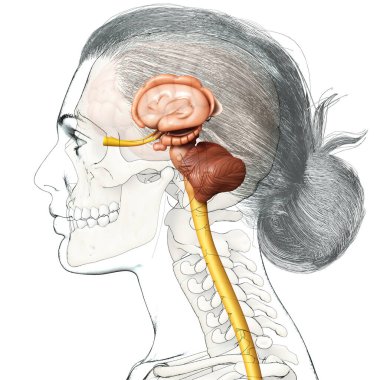

The arterial blood supply to the neck (carotids and vertebral arteries).